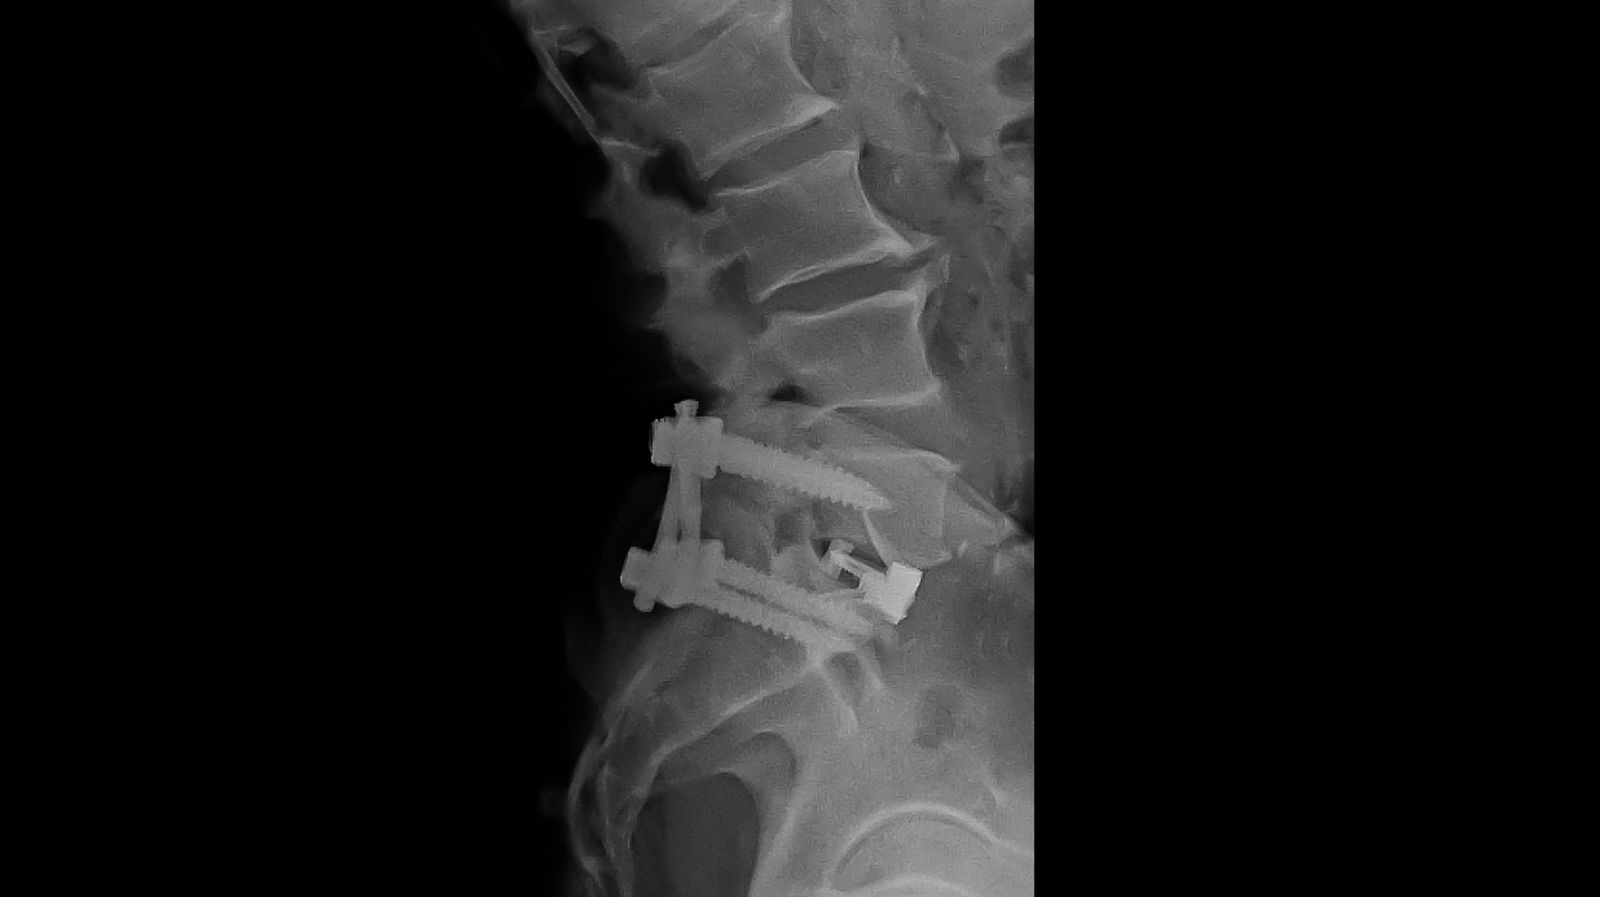

ALIF stands for Anterior Lumbar Interbody Fusion, a type of spinal fusion surgery for the lower back.

This is one method of performing Lumbar Interbody Fusion, wherein the degenerated disc is removed from the front through the tummy and the space fused together with a bone graft/cage.

Bone graft placement. Bone graft into the space where the damaged disc was removed. This graft may be taken from the patient’s body (such as the hip) or a synthetic or donor bone graft. Metal screws, plates, or cages help support and stabilize the spine while the bone graft heals. The incision is closed using sutures or staples.